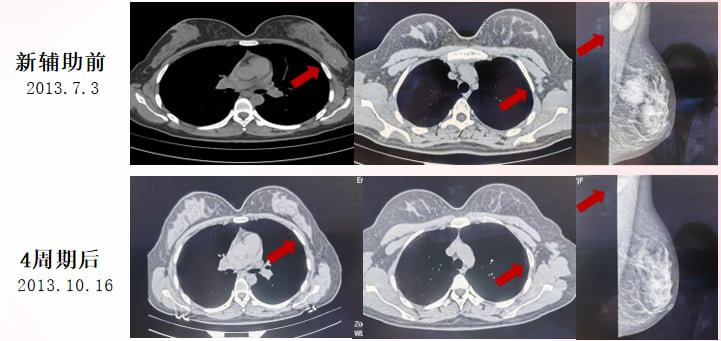

2013年7月,患者因发现左乳肿物10月余就诊。在MDT团队的指导下,她接受了规范的新辅助化疗(TAC方案4周期),取得了部分缓解(PR)。随后进行了左乳癌局部广切+左腋下淋巴结清扫手术。术后病理证实为浸润性导管癌,腋窝淋巴结有转移(9/13)。

术后辅助治疗包括:

- 辅助化疗:继续TAC方案2周期。

- 内分泌治疗:口服他莫昔芬。值得注意的是,由于患者年轻,存在生育需求,她在治疗期间曾间断服药。

- 放疗:左侧乳房及锁骨上下区三维适形放疗。

此后,患者定期复查,病情稳定。这段早期的规范治疗为她争取了宝贵的无病生存期(DFS)。